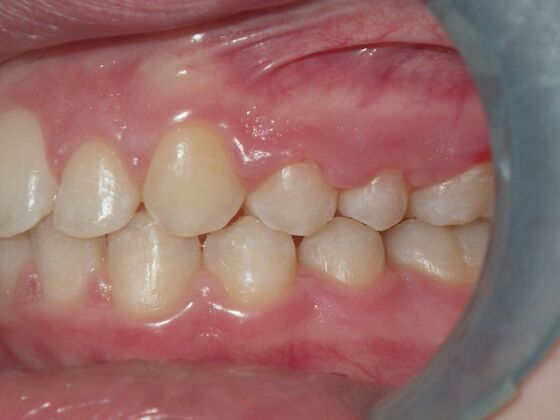

Orthodontics: Case 2

Patient is 9 years old and presents with 100% overbite and blocked out upper and lower lateral incisors. Both upper central incisors are palatally inclined causing a lack of space available for most anterior teeth. Advised her parents that she needs Phase I Interceptive Orthodontic treatment to provide room for all upper and lower front teeth. Phase I treatment was begun and finished, then began Phase II treatment shortly thereafter to finalize case. Removable retainer were fabricated for retention.